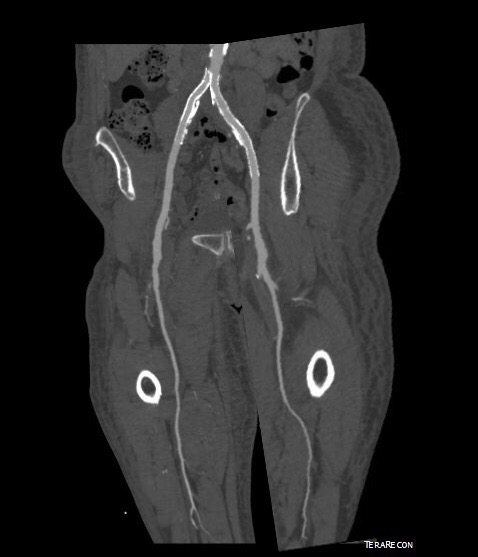

The remote endarterectomy of the external iliac artery remains patent. Compare this to the preop CTA which I found and wasn’t available when I posted this case originally:

The chronically occluded EIA can be readily seen. The artery shown in the current CTA is that recanalized artery.

CTA (pictured above and below) showed a 5.1cm infrarenal AAA with an hourglass shaped neck with moderate atherosclerosis in the neck, an occluded left common iliac artery with external iliac artery reconstitution via internal iliac artery collaterals, and a right external iliac artery occlusion with common femoral artery reconstitution. There was calcified right common femoral artery plaque.